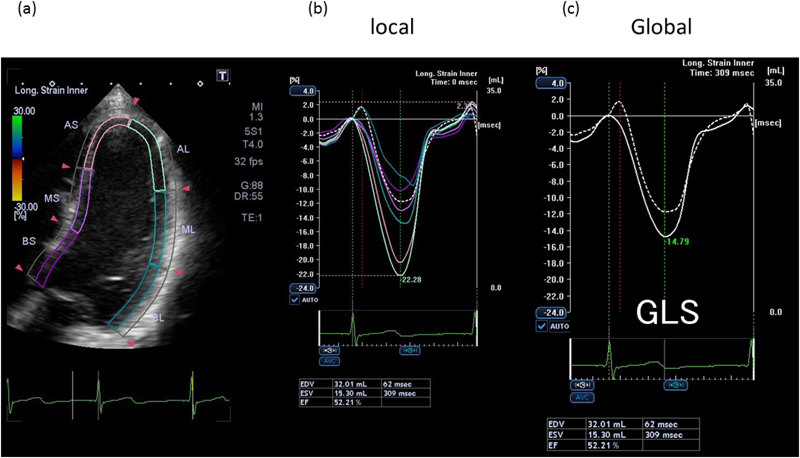

Pediatric Cardiology and Cardiac Surgery 32(2): 78-86 (2016)

Fig. 4 Examples of longitudinal strain curves

(a) Trace of the myocardium in the apical 4-chamber view; (b) local and (c) global longitudinal strains (GLS) in the patient after an arterial switch operation for transposition of the great arteries.

ここまでで得られた結果は,心筋の各部位毎の複数の時間–ストレイン曲線である.全体の平均的なストレインがグローバル・ストレインで,とくに長軸方向のグローバル・ストレインをglobal longitudinal strain(GLS)といい,心室全体の収縮性指標として最近報告が増加している8–11).GLSを表示するには,画面左上からFormatを選択し,左中のGlobalからonまたはonlyを選択するとGLSのカーブが得られる(Fig. 4(c))ので,そのピークの値を記録すればよい.文字での説明は長くなるが,実際は動画がきれいにとれていれば,1~2分程度の所要時間で,簡便に解析できる.その上で,肉眼でtrackingしていない部位があれば,その部位のストレイン曲線は計算から除外する.